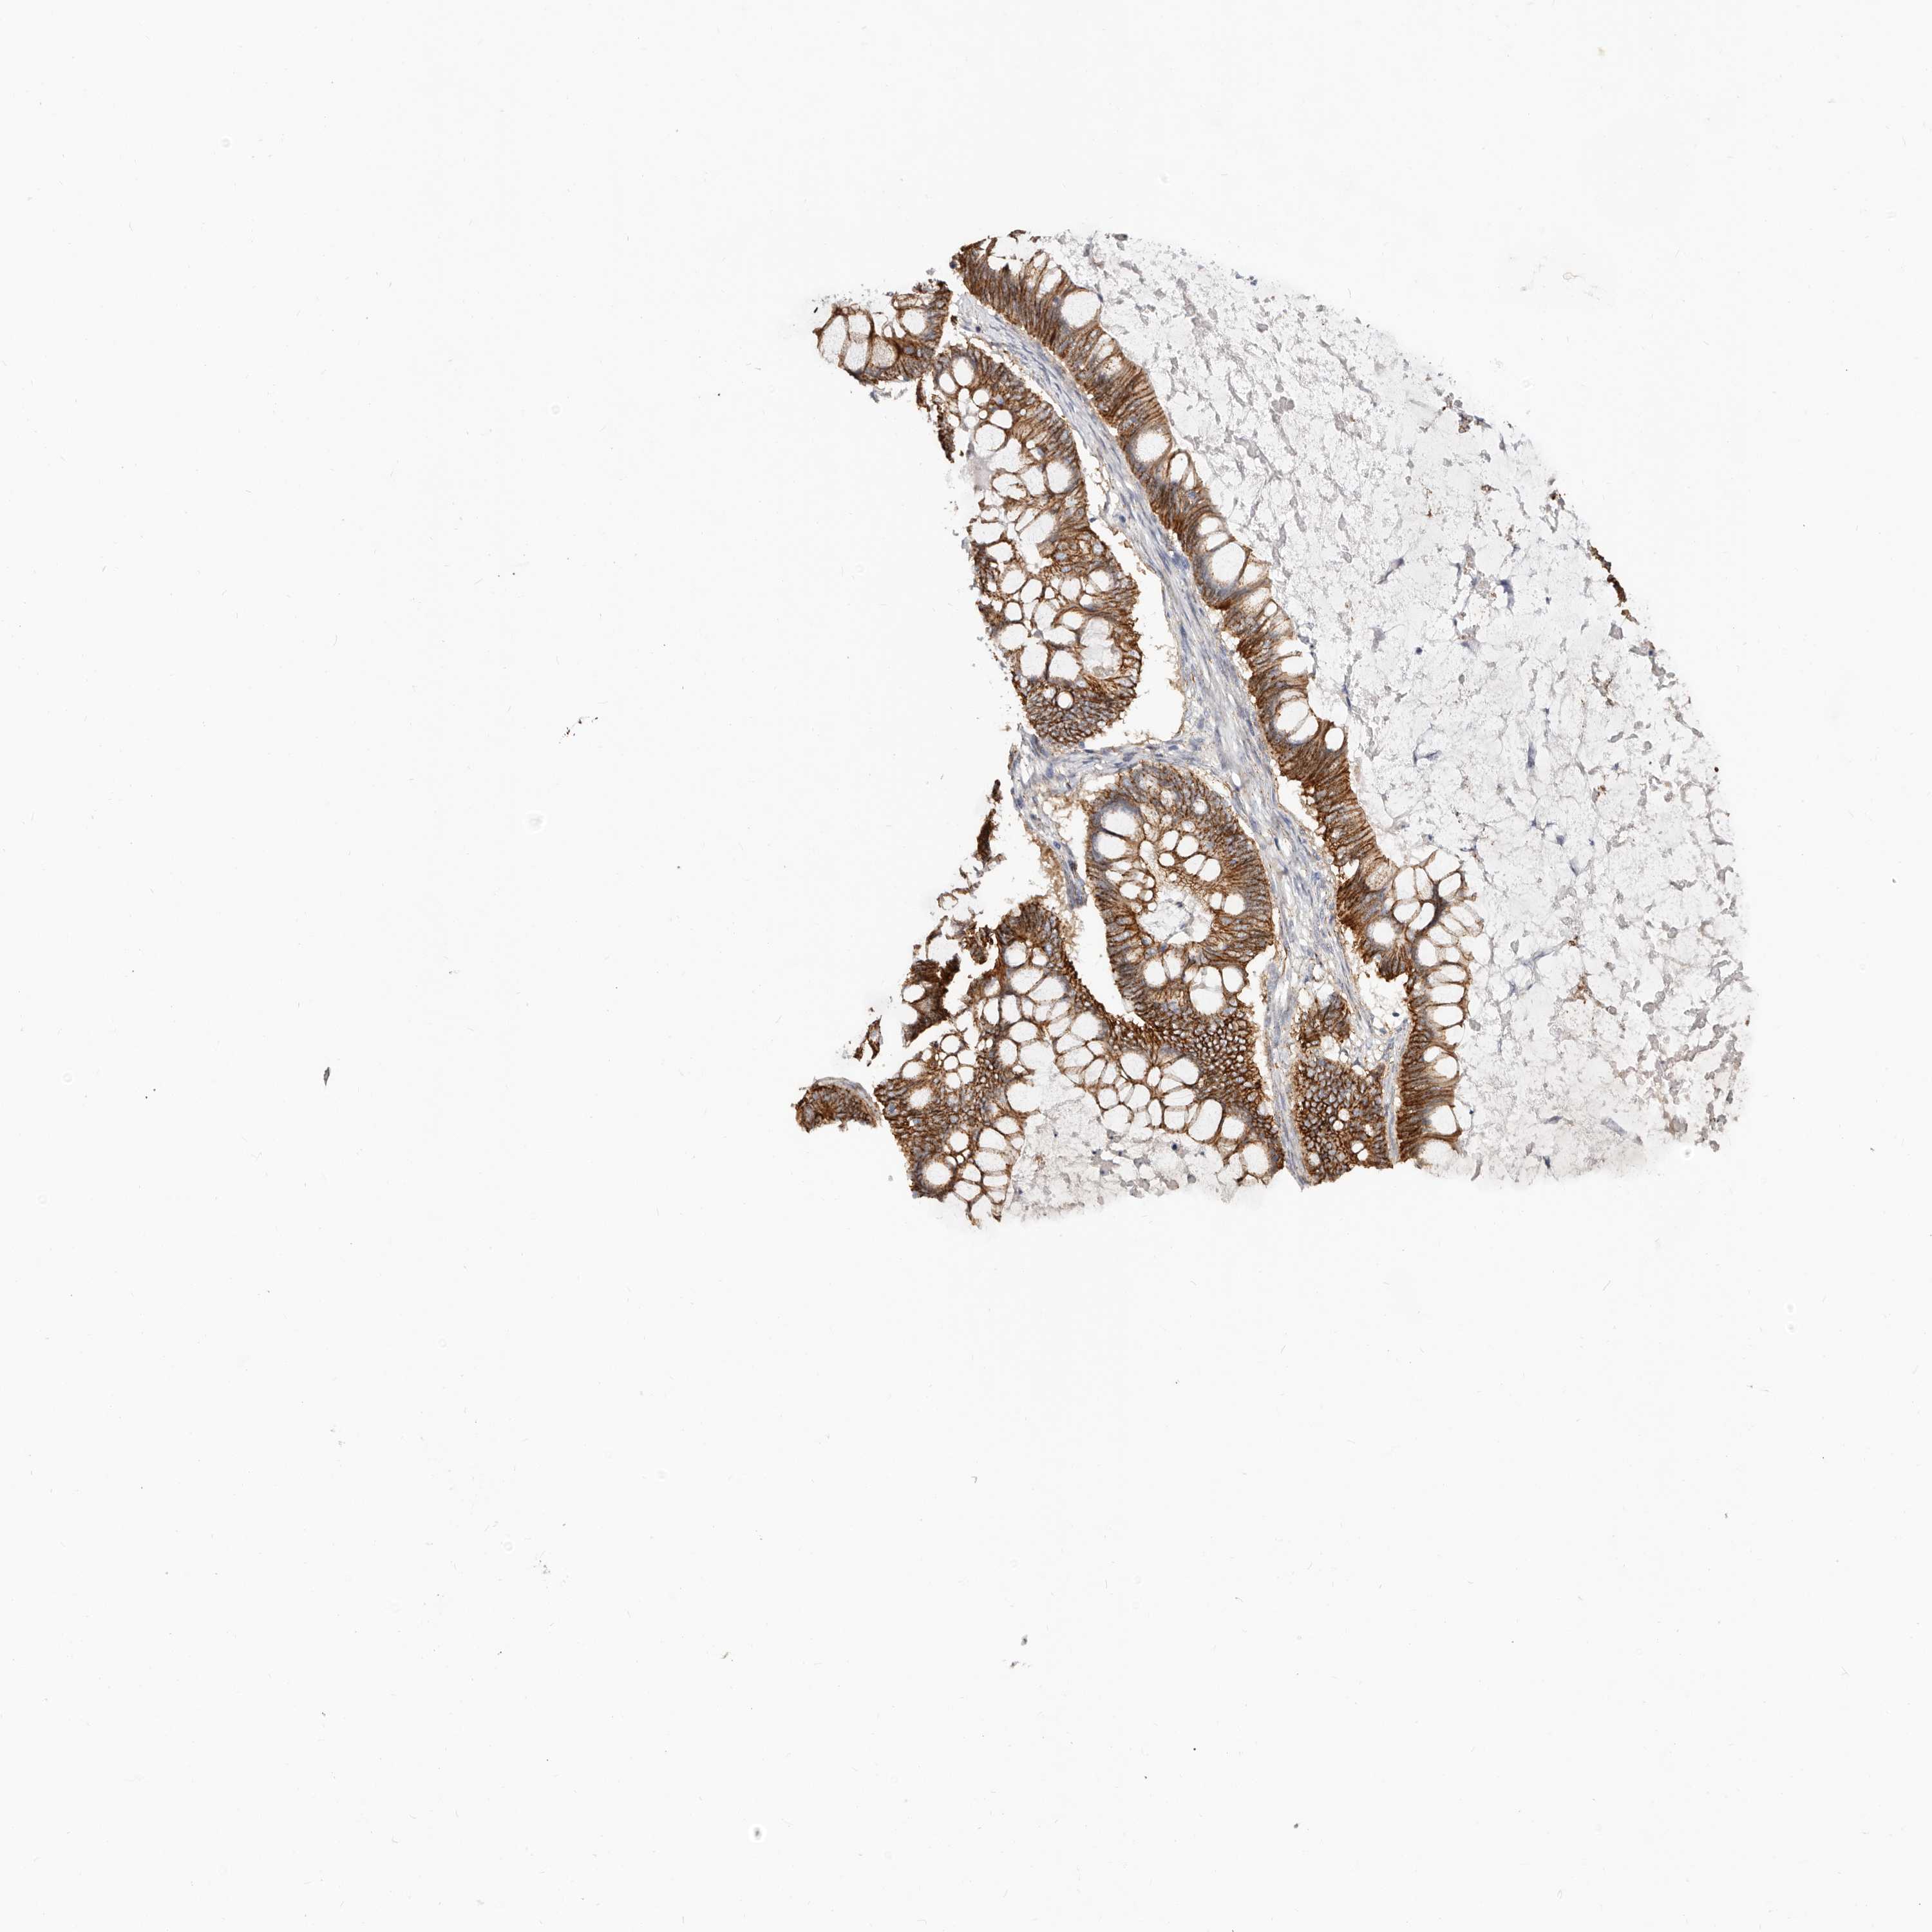

OVARIAN CANCER - Protein expressioni

A mouse-over function shows sample information and annotation data. Click on an image to view it in a full screen mode. Samples can be filtered based on level of antibody staining by selecting one or several of the following categories: high, medium, low and not detected. The assay and annotation is described here.

Note that samples used for immunohistochemistry by the Human Protein Atlas do not correspond to samples in the TCGA dataset.

Antibody stainingi

Antibody staining in the annotated cell types in the current human tissue is reported as not detected, low, medium, or high, based on conventional immunohistochemistry profiling in selected tissues. This score is based on the combination of the staining intensity and fraction of stained cells.

Each image is clickable and will lead to virtual microscopy that enables deeper exploration of all samples and also displays staining intensity scores, fraction scores and subcellular localization as well as patient and tissue information for each sample.

Antibody HPA029159

Antibody HPA029160

Antibody CAB000108

Antibody CAB001950

Staining

High

Medium

Low

Not detected

Intensity

Strong

Moderate

Weak

Negative

Quantity

>75%

75%-25%

<25%

None

Location

Nuclear

Cytoplasmic/membranous

Cytoplasmic/membranous,nuclear

Cystadenocarcinoma, serous, NOS

Carcinoma, endometroid

Cystadenocarcinoma, mucinous, NOS

Carcinoma, NOS